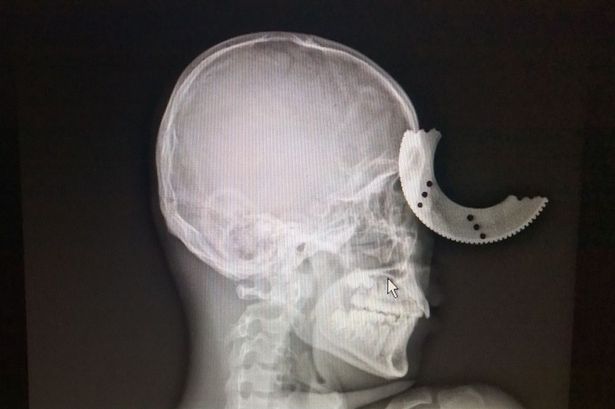

(Khám phá) - Dù bị lưỡi cưa “cắt xuyên hộp sọ” nhưng người đàn ông đã may mắn sống sót với di chứng bị suy giảm thị lực một bên mắt.

Đó là trường hợp của anh công nhân Zheng Lang, ở Phúc Châu (Trung Quốc). Cụ thể, khi đang sử dụng máy cắt điện để cắt thanh kim loại, đĩa cưa bất ngờ bị vỡ, văng ra và cắm thẳng vào trán anh Zheng Lang.

Ảnh chụp X-quang của anh Zheng Lang.

Nạn nhân cho biết, vụ tai nạn xảy ra quá nhanh nên ban đầu anh thậm chí không nhận thấy gì. “Tôi cảm thấy một cái gì đó chạm vào trán tôi và rồi máu chảy ra”, anh kể lại.

Anh được đưa đến bệnh viện cấp cứu ngay sau đó. Tại đây, bác sĩ nhanh chóng tiến hành phẫu thuật loại bỏ dị vật và các mẩu xương sọ bị vỡ.

Lưỡi cưa và các mảnh hộp sọ gỡ ra từ đầu Zheng Lang.

Điều khiến ai cũng bất ngờ là dù lưỡi cưa ngập sâu vào hộp sọ tới 2cm và khiến anh suýt mù cả 2 mắt nhưng Zheng Lang được chẩn đoán sẽ nhanh chóng hồi phục. Sự cố kinh hoàng chỉ để lại di chứng nhẹ về suy giảm thị lực một bên mắt.